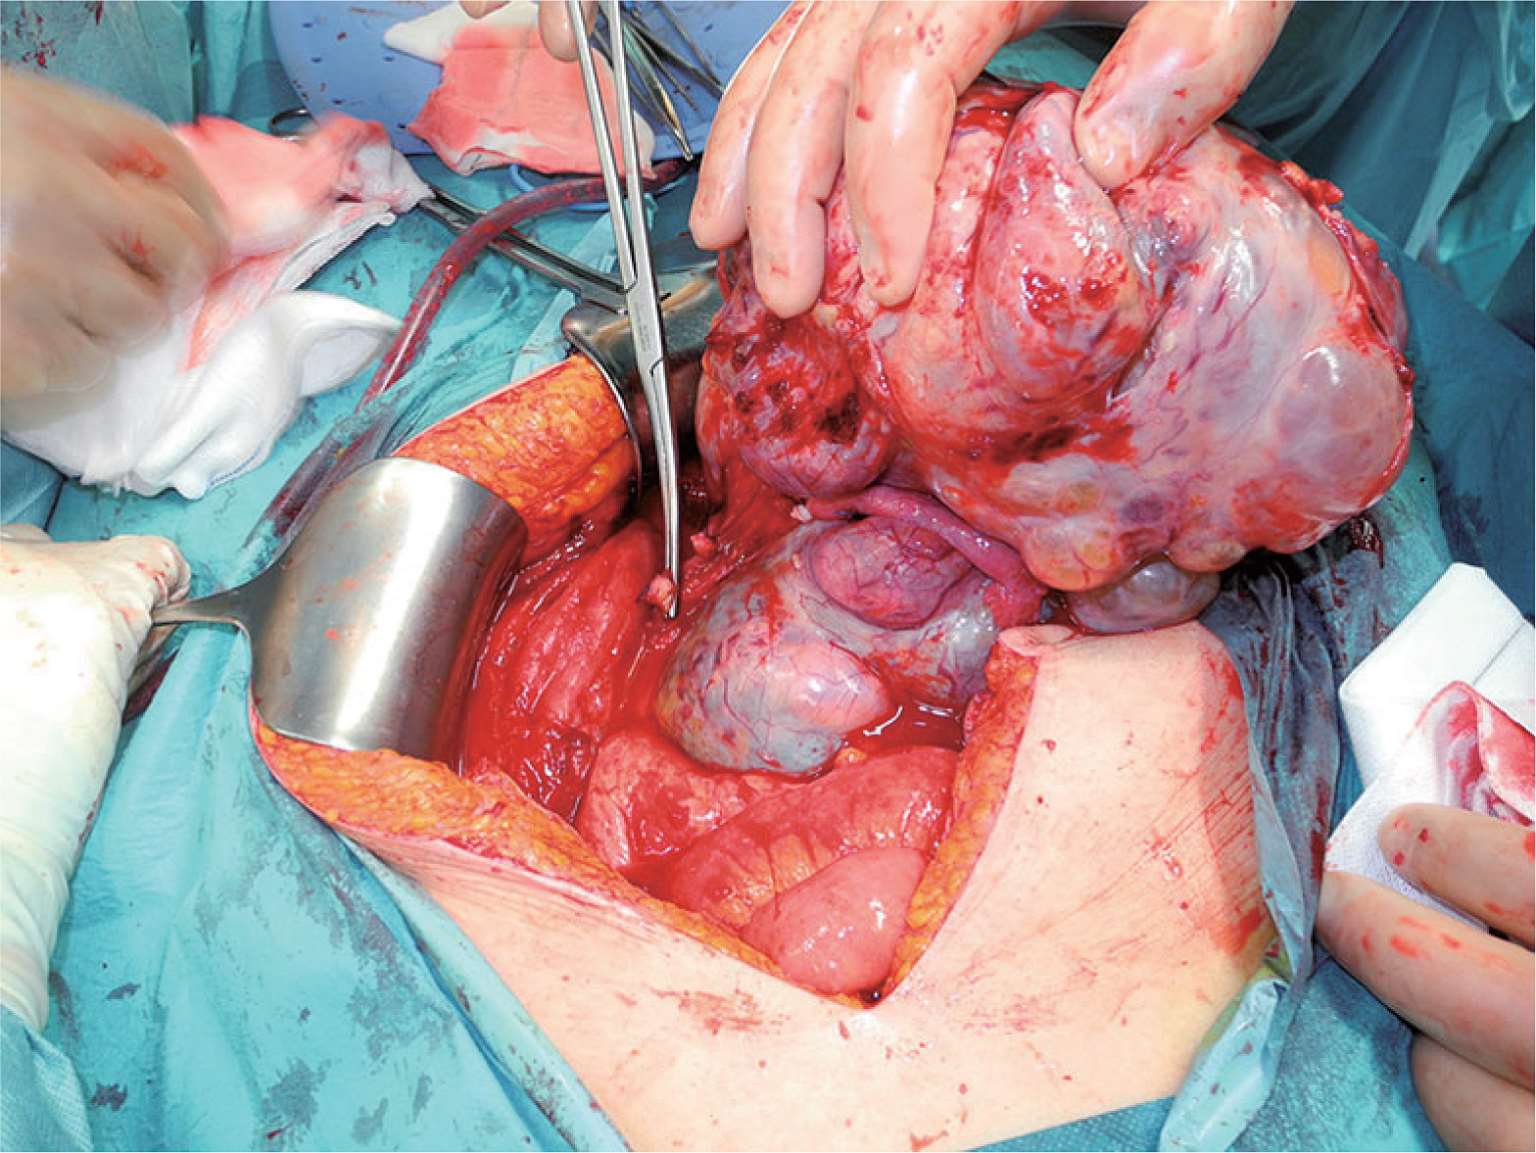

图2-14 一罕见病例,巨大Krukenberg瘤,占据超过一半的腹腔容量,导致腹腔筋膜室综合征。

图2-15 切除图2-14所示肿瘤。